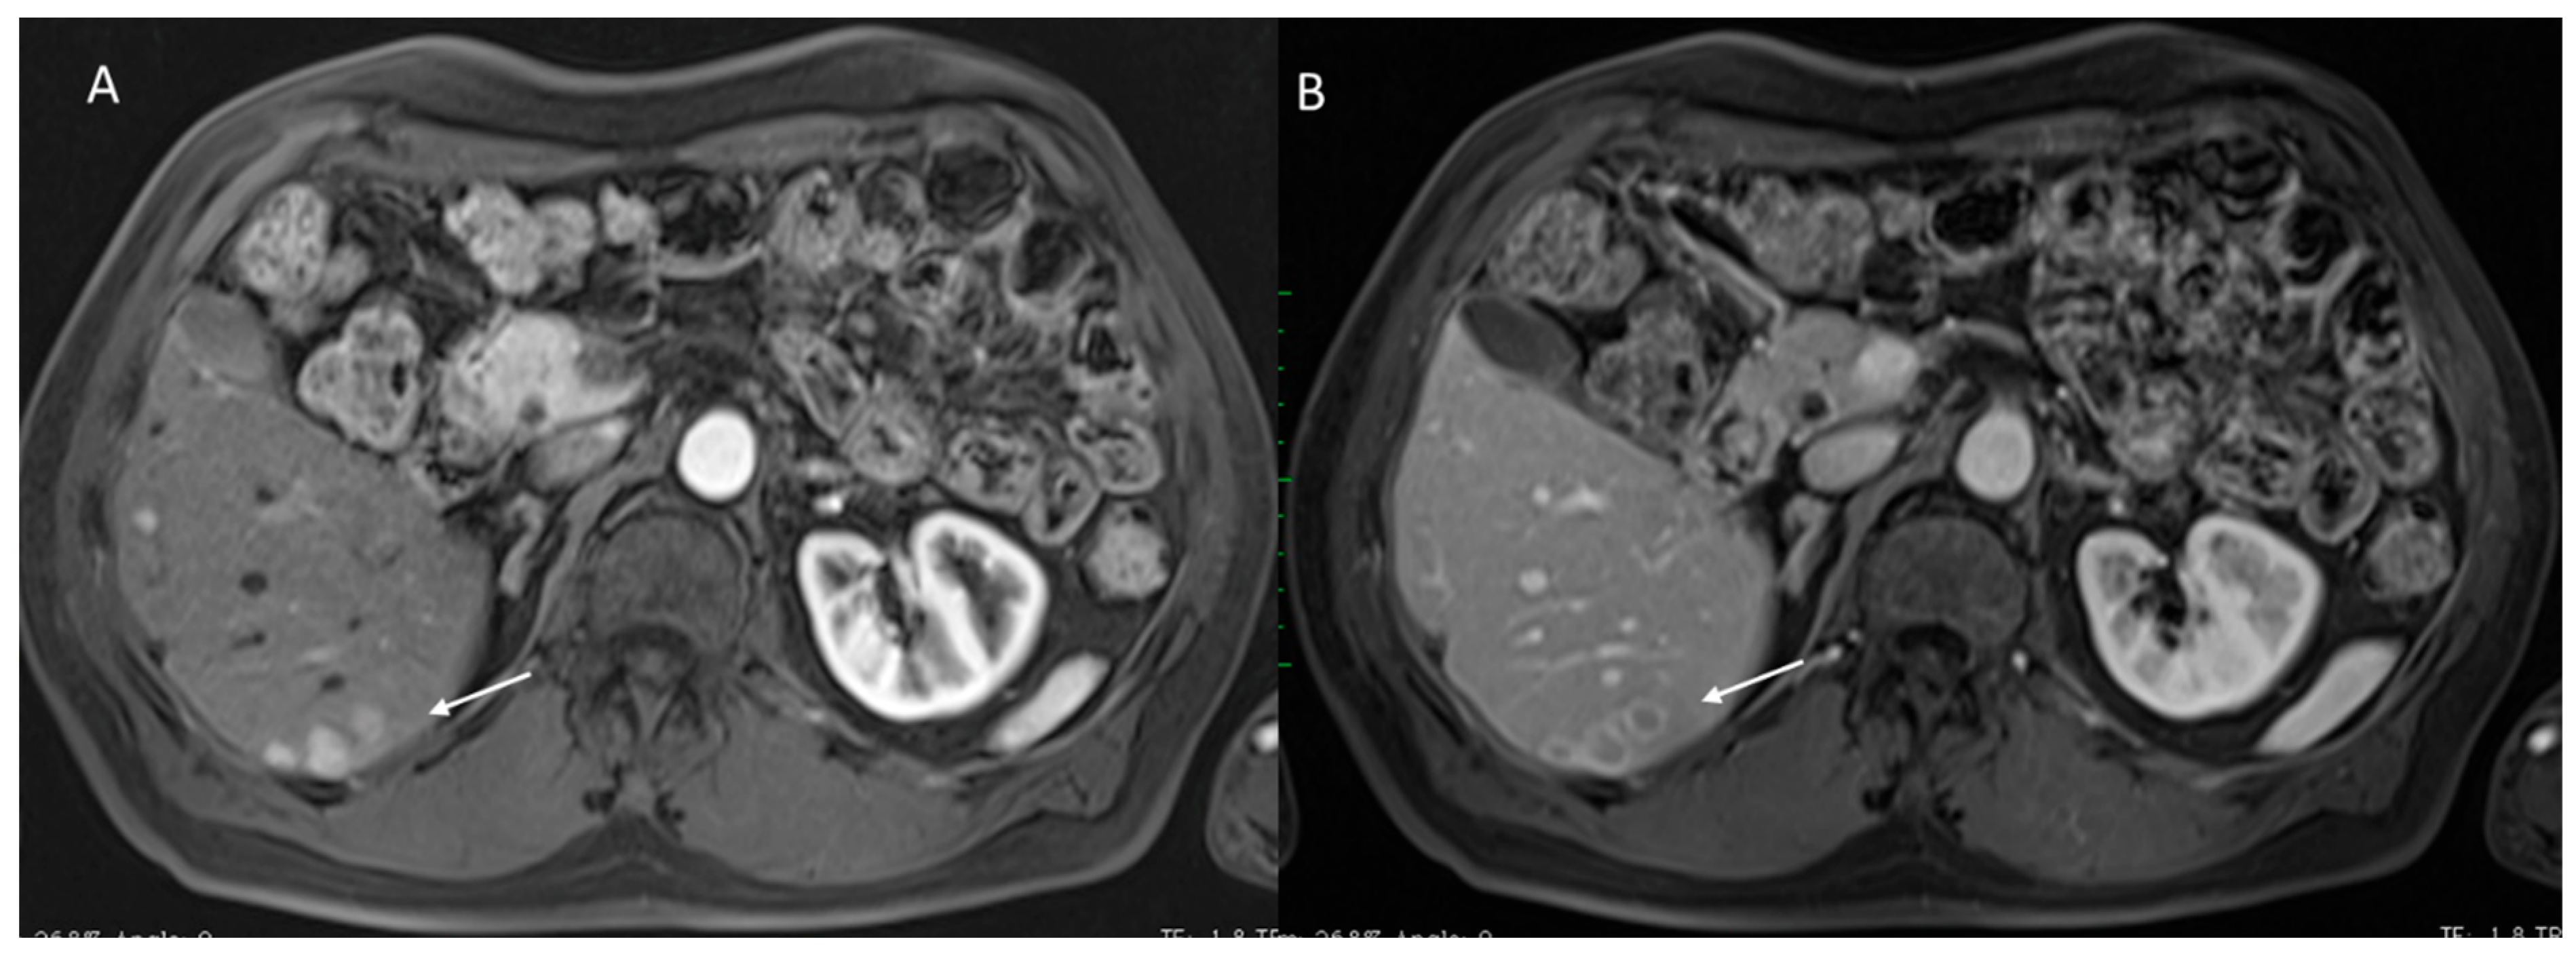

2.2. CT/MRI LI-RADS

2.2.2. CT/MRI Categories

2.2.3. HCC Diagnosis

2.2.4. Ancillary Features